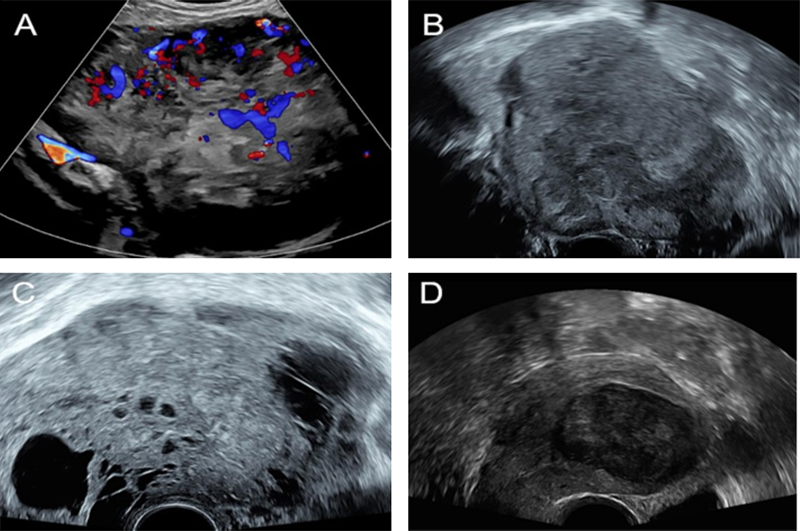

학회가 전하는 초음파 소식 Ultrasound in the Assessment of Obstetric hemorrhage and Postpartum Uterine Abnormalities 2026-02-02 부인과 수술에서 수술 중 초음파(IOUS)의 역할과 최신 임상 응용 2026-01-06 New insights into functional imaging of the placenta 2025-12-01 더보기